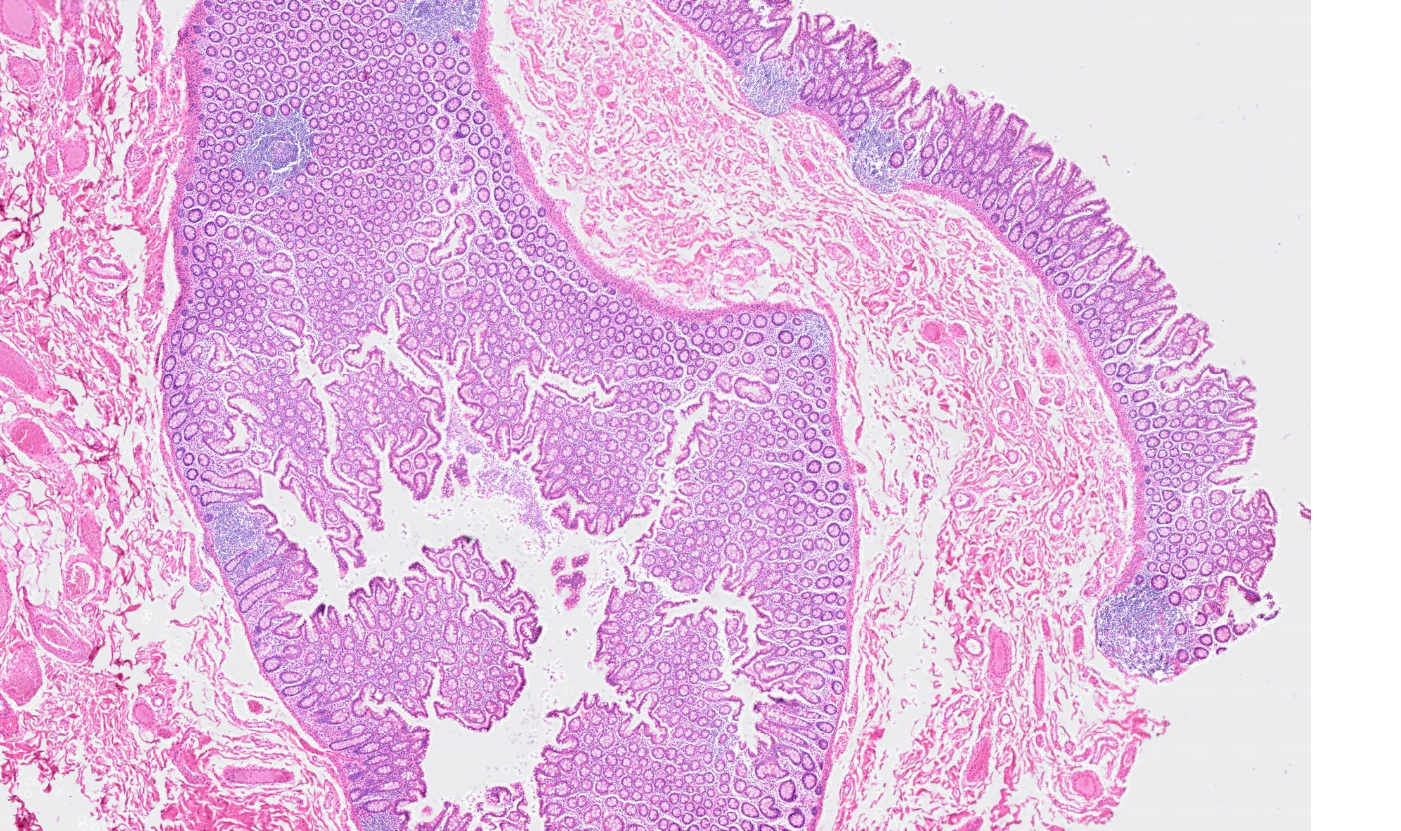

Applicability across many tissue types

The segmentation module is designed to generalize across a wide range of biological tissues. Below are representative benchmark results based on 10x Genomics demo datasets:

Colon